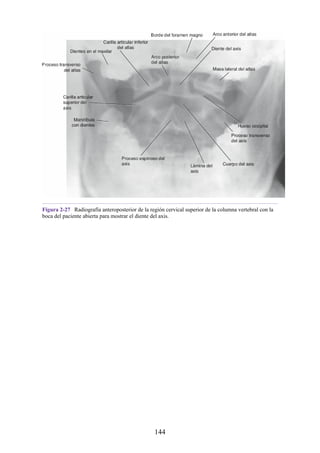

encéfalo y en algunos segmentos sacros de la médula espinal (véase fig. 1-23).

Las del tronco del encéfalo forman parte tanto de los núcleos de origen de los